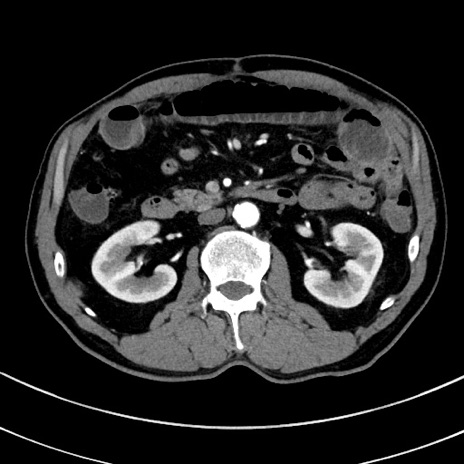

症例8(横断像)

【症例】 60歳代男性

【主訴】 黒色吐物

【現病歴】 4日前から嘔気自覚、2日前の朝食後にも嘔気あり、自分で手で嘔吐反射起こし嘔吐したところ血が混ざっていたため受診。

【既往歴】 5年前汎発性腹膜炎を伴う急性虫垂炎で手術、高血圧、前立腺肥大症、高脂血症

【身体所見】 腹部正中に手術癩痕あり 腹部平坦・軟圧痛なし膨満感あり

【データ】WBC 8400、CRP 4.54